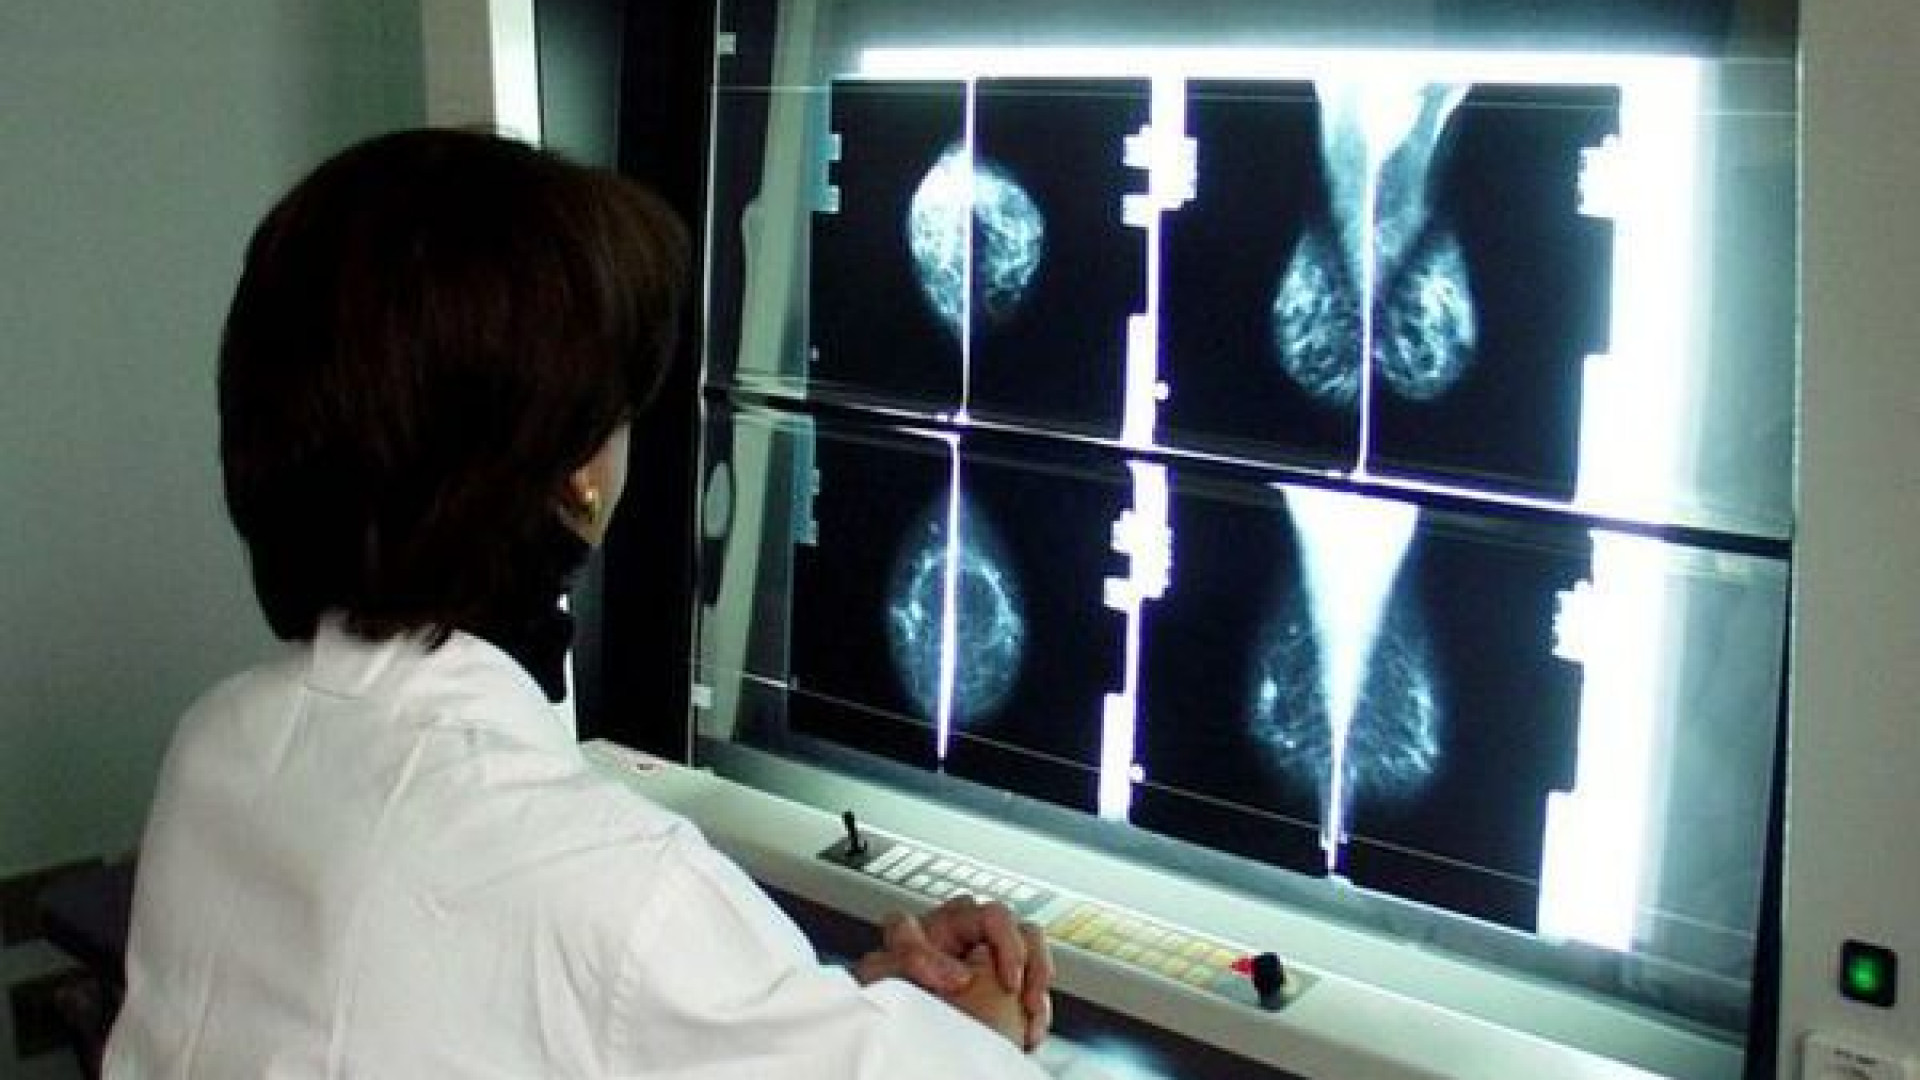

“Abbiamo effettuato 20.550 mammografie di screening nel 2018 – ha spiegato la responsabile – in linea con i numeri degli anni precedenti ma vorremmo raggiungere percentuali molto più alte”. Gli esami clinici sono stati 5.500 e le ecografie oltre 8mila. Numeri importanti che fanno della struttura un centro di eccellenza. “Qui lavoriamo a pieno ritmo e devo ringraziare tutta l’equipe per il prezioso sforzo. Il tumore al seno, se trovato in tempo, può essere curato, prima ci si sottopone ai dovuti controlli più alte sono le possibilità di farcela”.

Si tratta di una patologia che può colpire gli uomini anche se più raramente. “Abbiamo trovato 4 pazienti positivi che sono stati sottoposti a un intervento chirurgico risolvendo il problema”. Il centro segue anche 200 donne ad alto rischio che vengono valutate ogni 6 mesi. Nel 2018 i tumori riscontrati sono stati 390 e la maggior parte delle pazienti è stata indirizzata al percorso senologico. La novità di quest’anno è che le malate oncologiche, per i primi 10 anni, vengono completamente prese in carico dal centro salute donna e seguite in un percorso di controlli garantito.